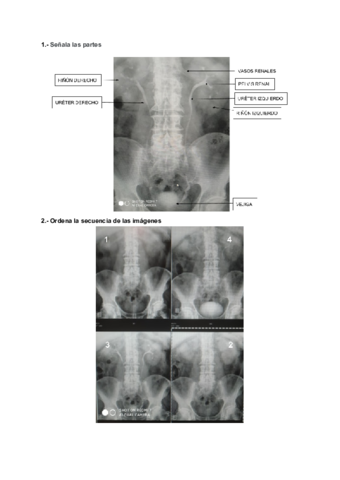

Apuntes - RE-TEMA-SISTEMA-GENITOURINARIO.pdf